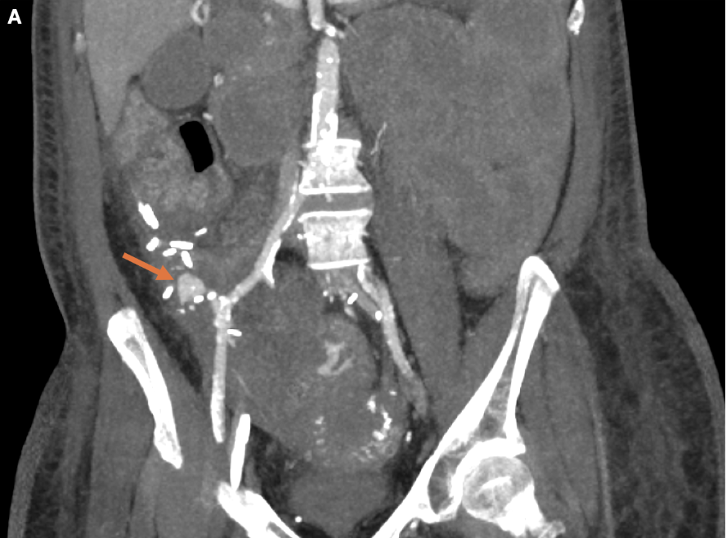

Diagnostic/Laboratory Testing. A computed tomography angiogram (CTA) of the abdomen and pelvis performed after initiating the massive transfusion protocol showed brisk arterial bleeding in the jejunal loops and a 1.6 × 0.9 cm pseudoaneurysm near the pancreatic transplant anastomosis (Figure 1).

Figure 1. Thick multiplanar reformatted (MPR) coronal computed tomography (CT) in the arterial phase demonstrates a large pseudoaneurysm (arrow) arising from the pancreatic transplant arterial anastomosis.